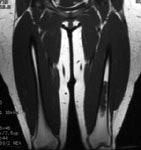

Ewings sarcoma of the pelvis: The bone scan demonstrates extensive, intense tracer uptake involving the left iliac wing, extending into the ischium and left sacrum. CT scan revealed a mixed, but predominantly sclerotic lesion involving the bone with an associated soft tissue mass. Note that the sacrum fails to demonstrate a CT abnormality. The T2 weighted images from the patients MR exam more clearly defines the lesion. Sacral involvement is clearly evident (white arrows) and there is also a large soft tissue component. |